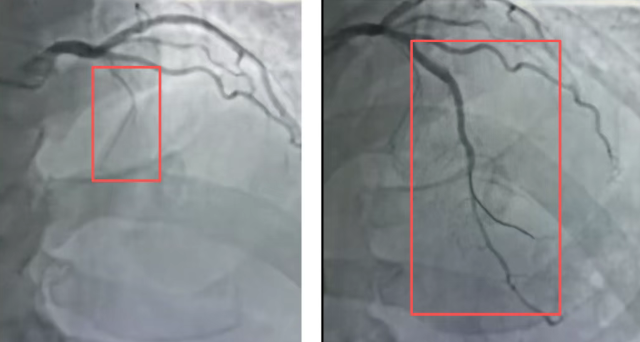

患者苏先生(化名),因间断胸痛、胸闷2年来到国文医院。此前,他并未对这些反复出现的症状给予足够重视,直到近期不适感明显加剧,才决定就医。入院后,冠脉造影结果提示:其冠状动脉前降支(LAD)在发出对角支后100%闭塞,血管壁钙化严重,质地坚硬,属于典型的严重钙化慢性完全闭塞病变(CTO)。这类病变在冠脉介入治疗中难度较大,对术者的技术和团队协作能力提出了较高要求。

术中,团队首先尝试正向开通,但因钙化病变坚硬,导丝难以推进。随即,术者调整策略,采用“对侧穿刺”技术,从右侧桡动脉建立通道,借助对侧血管造影影像进行精准指引。在微导管支撑下,选用高穿透力导丝,经过精细操作,最终成功通过闭塞段。随后,团队依次使用不同规格球囊对病变血管进行充分预扩张,经评估后植入两枚支架,成功开通闭塞血管。